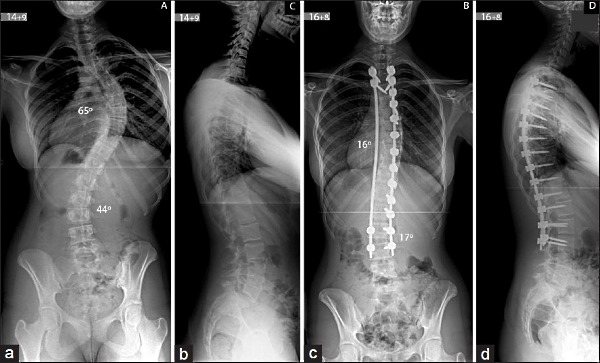

Хирургическое лечение

Хирургический метод исправления кривизны позвоночника применяется, если достигнута третья степень развития патологии. Обычно она достигается уже в том возрасте, когда активны рост человека прошел (более 15 лет), а позвонки и ткани еще достаточно эластичны.

Операция выполняется в два этапа:

- удаляют межпозвоночные диски на вершине дуги;

- производят рассечение мышц на протяжении всей деформации, высвобождают заднюю стенку позвонков от мягких тканей, выполняют остеотомию на вершине дуги.

Далее следует производить установку имплантов.